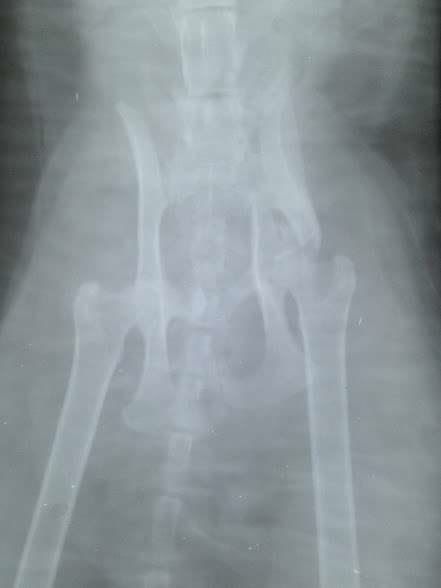

To save an animal does not mean to give a call or write a message and wait for the case to be solved. Unfortunately, many people think we are some sort of ANIMAL PLANET but in reality we make great efforts to cope with so many cases of accidents, abandonments, torture cases, especially since we don’t have a medical Office or veterinarian for the association; we go to medical offices where, through the goodwill of the doctors, we recieve discounts, but this does not mean there are no large costs and atferwards we take it upon ourselves to house the saved animal for life, regardless of the fact that it can remain with 2 or 3 legs, or blind for life. This is the way we transformed our home into a small sanctuary for nobody’s animals but now ours, and for this, many people think we receive money for these animals, because they are handicapped. False, many times we do not have enough to cover the medical bills, but after discharge we take them in and take responsibility for their care. This is how we received a phone call that a cat is lying unable to walk for some time, with her legs crushed, asking us to do something for her. So we did just that, we posted on social media asking for help with the transport to a clinic where we allready spoke for her. Fortunately, we found a person quickly and the poor kitty arrived at the clinic where she was hospitalized. But her state is very bad, a leg needs to be amputated and the spine is also fractured. But no matter if she remains with 3 legs or paralyzed, we will become her home from now on.